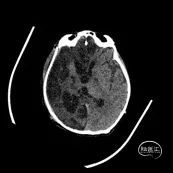

术后1周